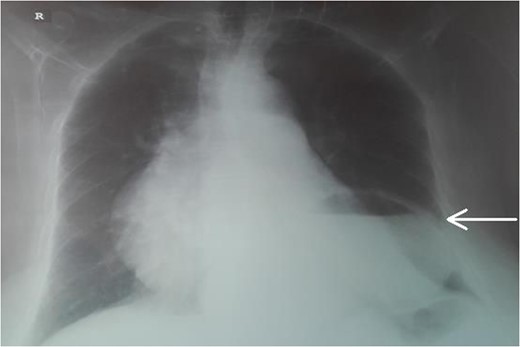

An 87-year-female patient was admitted to emergency department complaining about vomiting for the past 7 days with mild abdominal pain. The patient was hemodynamically stable, had sluggish bowel sounds and soft abdominal wall with mild tenderness. The patient also suffered from atrial fibrillation, heart failure, myelodysplastic syndrome, hiatus hernia and cholelithiasis. The findings of the laboratory tests were unremarkable. Plain chest and abdominal radiograms revealed hiatus hernia with gastric dilation (Fig. 1), a few air-fluid levels and pneumobilia, with delineation of extrahepatic and intrahepatic bile ducts by air (Fig. 2). A nasogastric tube was inserted, which drained biliary content. An abdominal computed tomography (CT) scan revealed the presence of air in the intrahepatic bile ducts, free air and leakage of oral contrast agent in the hepatic hilum and subhepatic space and an impacted gallstone in the third portion of the duodenum (Figs 3 and 4). The diagnosis of cholecystoenteric fistula and proximal gallstone ileus was set.

Abdominal radiogram. The arrow shows the air in the bile ducts.